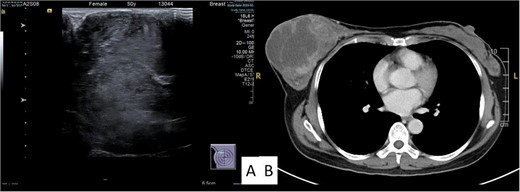

Examination revealed a firm, lobulated mass, measuring ~12 × 14 cm, predominantly occupying the breast, with the overlying skin remaining unaffected (Fig. 1A). No signs of skin ulceration, nipple inversion, discharge, or enlarged axillary lymph nodes were observed. Mammography indicated a well-defined, high-density lobular tumor measuring 12 cm, lacking any of calcifications (Fig. 1B). Breast ultrasound revealed a well-defined homogenous hypoechoic mass lesion larger than 10 cm (Fig. 2A). CT scan confirmed a heterogeneous soft tissue lesion within the breast, with no evident involvement of the chest wall, axillary lymph nodes, or distant metastasis (Fig. 2B).